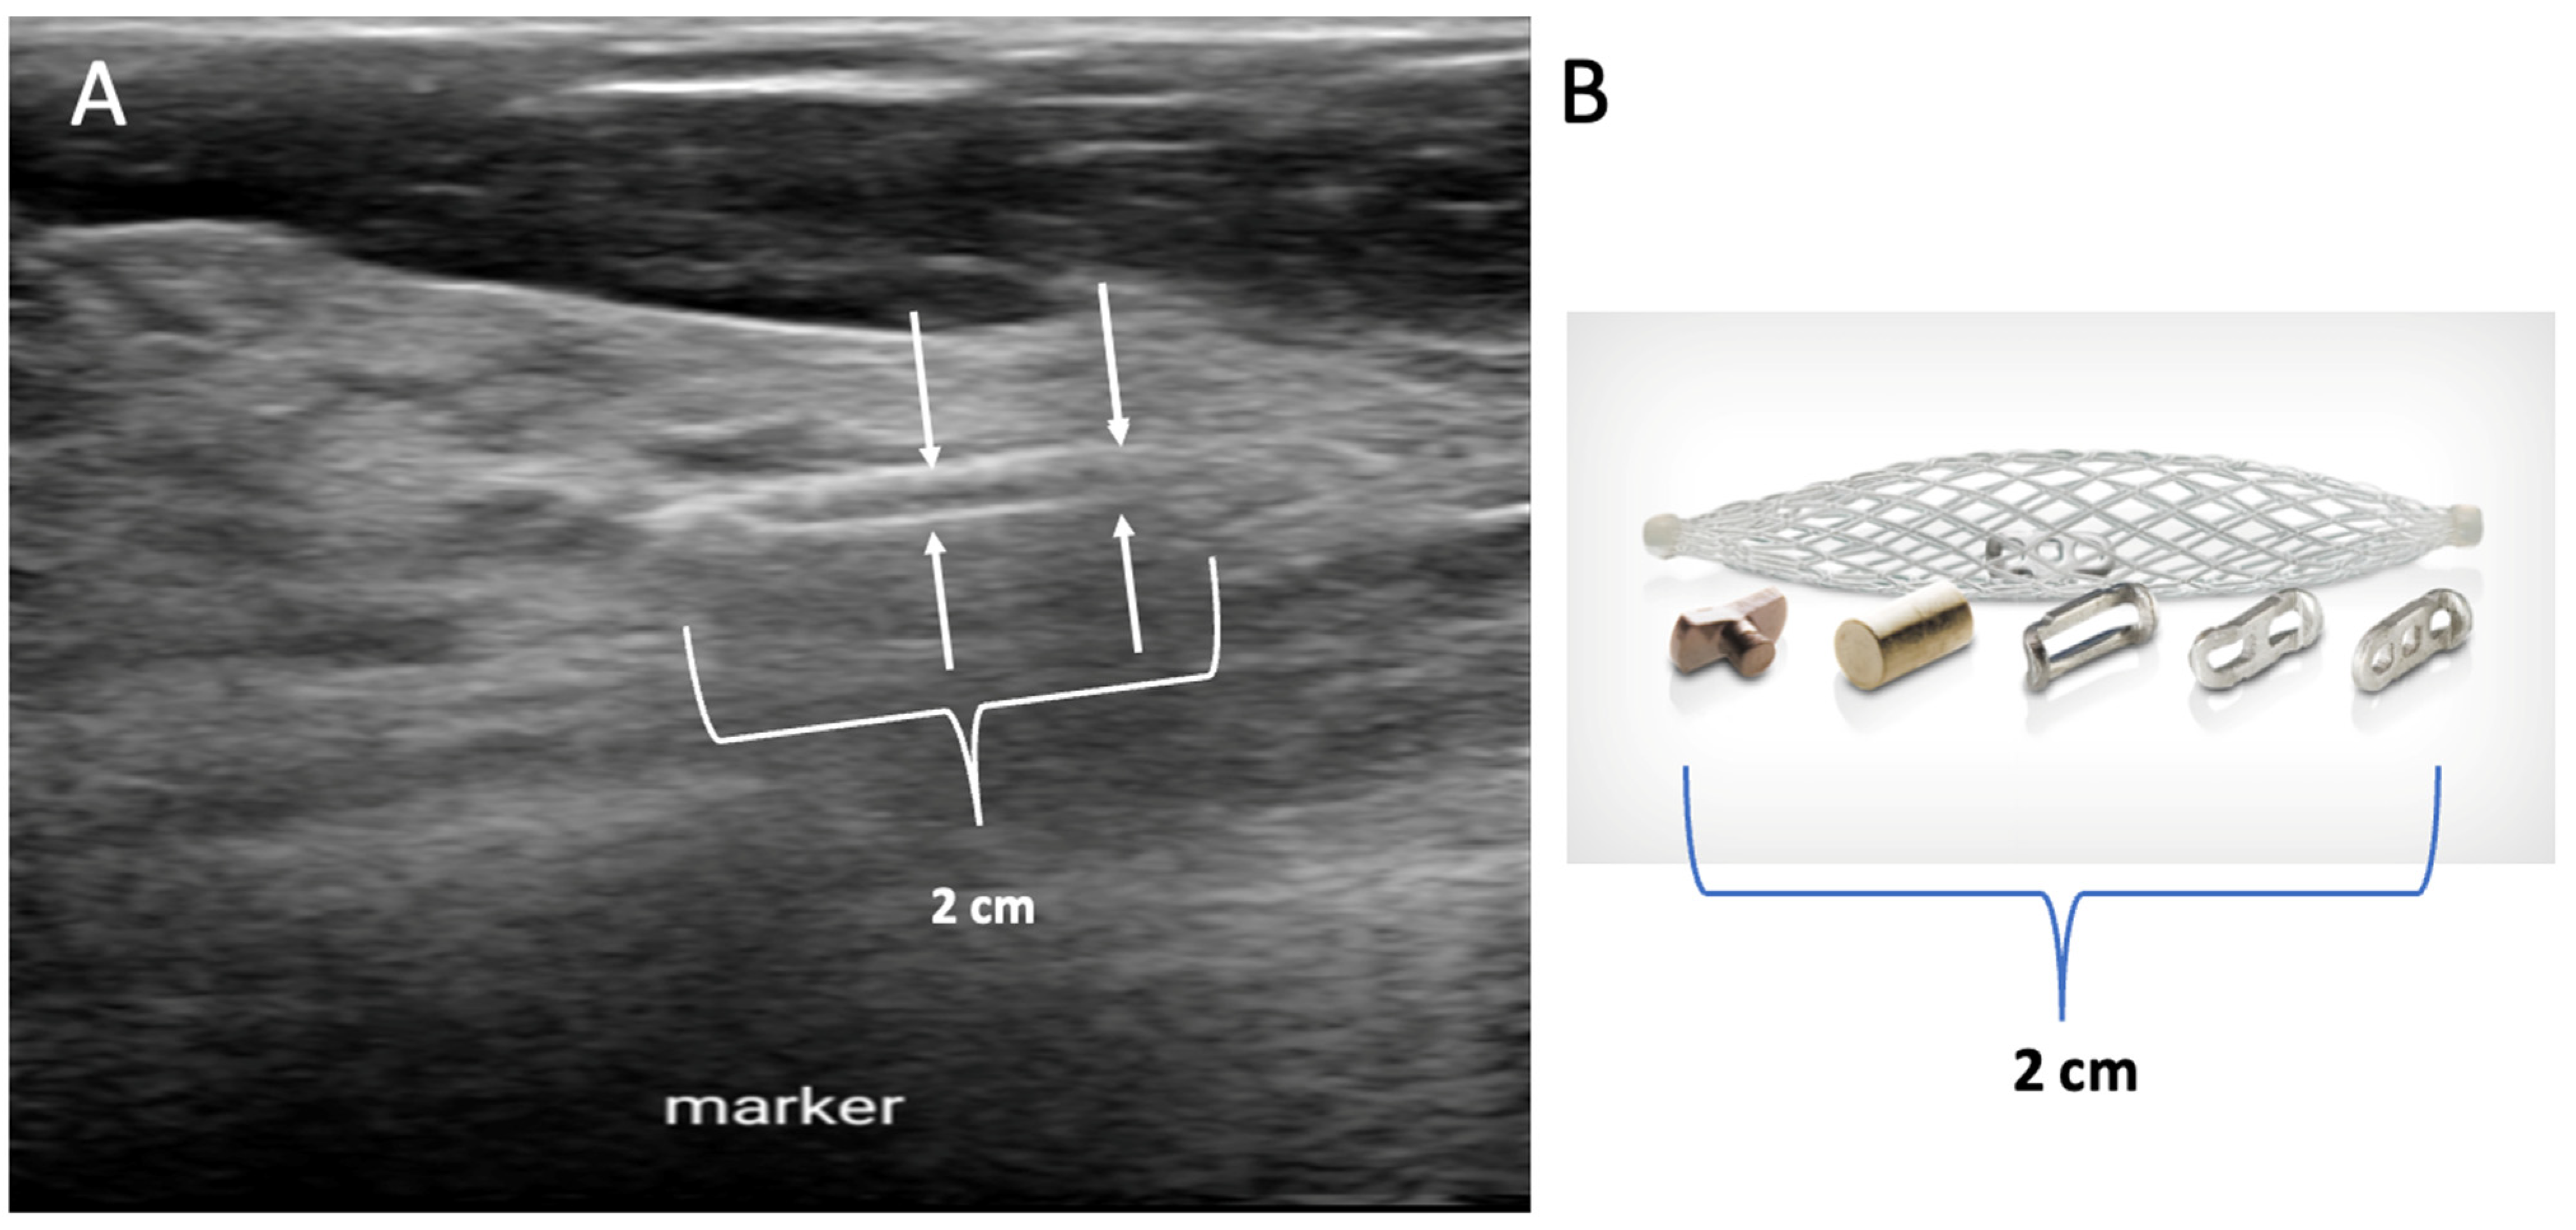

Biopsy site markers come in many shapes and sizes, but most measure less than 10 mm in length. In breast radiology, the most commonly used biopsy site markers are metallic (stainless steel, titanium, or nickel) devices that are optimized for detection by mammography, but are poorly visible by ultrasound. However, several biopsy site markers have been optimized for ultrasound detection by encasement of the metallic component in a larger, absorbable collagen or hydrogel sleeve (Figure 6). For cancers that are already visible by ultrasound, the type of marker is unimportant as the tumor itself provides an obvious target for ultrasound-guided cryoablation. However, when the breast cancer is very small or invisible to ultrasound, insertion of an ultrasound-visible marker at the time of the initial needle biopsy or subsequently will facilitate ultrasound-guided cryoablation of ultrasound-occult cancer.

Figure 6.

Ultrasound image (A) showing an example of a 2 cm long, basket-like, tubular, ultrasound-visible biopsy site marker (bracketed by paired arrows) that documents the location of ductal carcinoma in situ, which itself was not ultrasound visible. Image (B) shows an enlarged view of an actual basket-like marker and the shapes of various radio-opaque markers they may contain.

Generally, a single biopsy site marker is sufficient for marking the site of most breast cancers. However, patients with a wide span of disease may benefit from placement of two or more ultrasound-visible markers to outline or bracket the borders of the cancer to improve targeting of the cryoablation treatment (Figure 7).

Figure 7.

Mammogram showing the metal components (indicated arrows) of two ultrasound-visible biopsy site markers on opposite sides of the original metal biopsy site marker (encircled by hash marks) that was placed at the time of the diagnostic needle biopsy. The original biopsy site marker was not an ultrasound visible.